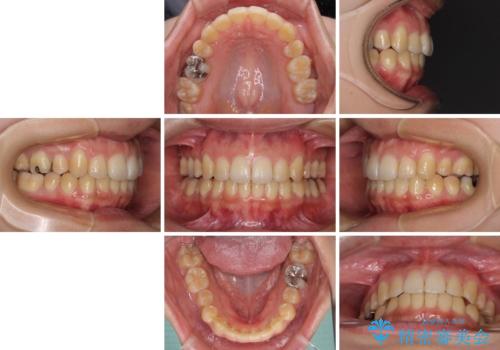

- 下の前歯のデコボコを気にして来院された患者様です。

来院当初、上顎の八重歯は気にしていらっしゃらなかったのですが、矯正治療をするのであれば、しっかりと治した方が良いと説明し、全顎矯正を行うこととしました。

八重歯の移動量が多く、インビザライン単体での治療は困難と判断し、補助装置により八重歯移動後にインビザラインを用いることとしました。

装着時間をしっかりと守ってくださったので、予定通りの期間で終了することができました。